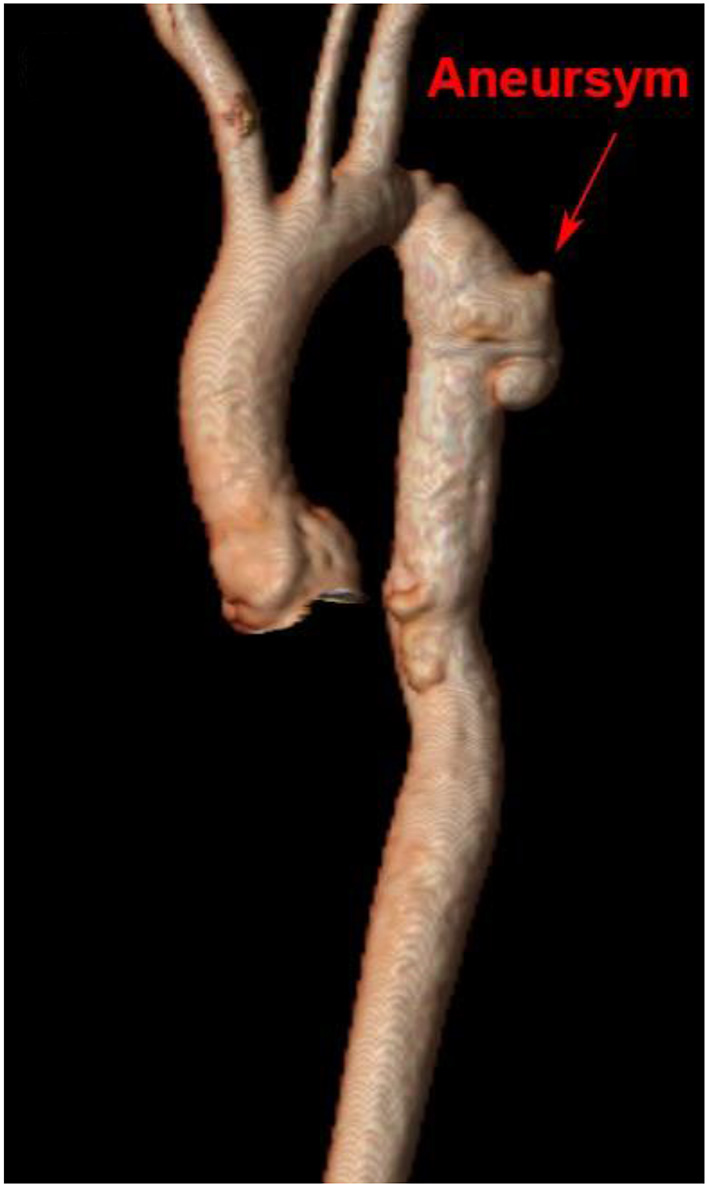

Recoarctation and Aneurysm Formation in Adults

Aortic aneurysm following CoA remains a life-long risk due to variations in vascular post-repair response that may impact growth and remodeling. Clinically significant recoarctation and/or aneurysmal dilation, diagnosed by MRI or CTA, occurs in nearly 10 and 13% of adult patients, respectively [(103), Figure 6]. Restenosis is more likely to occur after conventional resection with end-to-end anastomosis, while aneurysm formation is more frequent following surgical patch and older age at repair (132). Use of Dacron patch material is associated with a higher incidence of aneurysm formation (19–42%), morbidity, and mortality (133, 134). Reintervention for aneurysms distal to the isolated CoA repair may be performed surgically or by transcatheter approach, depending on the anatomy with a high rate of success. Fortunately, dissection following isolated CoA repair remains rare (135) and may be due to intrinsic abnormalities in the vascular wall rather than hemodynamic sequelae.

Figure 6

Cardiac magnetic resonance imaging after isolated CoA repair with aneurysm formation. 3D reconstruction of a patient's aorta with a Gothic arch and aneurysm formation at the site of prior isolated CoA repair.